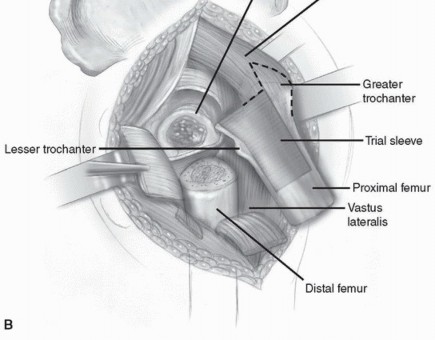

Femoral Preparation

Following acetabular preparation and component insertion, attention is turned to the femur. The femur is elevated and mobilized. Adequate soft tissue release, including release of the gluteus maximus insertion on the linea aspera if necessary, is performed to allow straight-line access to the femoral canal.

The femoral canal is initially opened with a box osteotome or starter awl, ensuring lateralization into the greater trochanter to prevent varus malalignment of the stem.

Distal Preparation: For modular stems utilizing diaphyseal fixation (typically fluted, tapered, or cylindrical distal stems), rigid straight reamers are utilized. Reaming is performed sequentially until cortical chatter is achieved, indicating rigid diaphyseal engagement. The depth of reaming is dictated by preoperative templating and the specific implant design.

Proximal Preparation: Once the distal canal is prepared, a trial distal stem is inserted. Proximal preparation is then performed over the trial distal stem or a guide wire to ensure the proximal metaphysis is prepared coaxially with the distal diaphysis. Depending on the system, this involves sequential proximal milling or broaching. The proximal body size is selected to provide rotational stability and to fill the metaphyseal bone without causing cortical fracture.

Trialing and Assembly

With the distal trial and proximal trial body in place, trial necks and heads are applied. This is the critical juncture where the modularity is leveraged. The surgeon can independently rotate the proximal body or modular neck to set the femoral anteversion, independent of the distal stem's position in the diaphysis.

The hip is reduced, and a comprehensive stability examination is performed. The hip is taken through a full range of motion, checking for impingement, soft tissue tension, and tendency for dislocation in flexion/internal rotation (posterior instability) and extension/external rotation (anterior instability). Leg lengths are assessed by comparing the level of the medial malleoli or by intraoperative measurement from a fixed pelvic pin to a point on the femur.